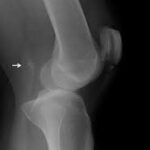

A careful clinical exam and the use of stress x-rays are very useful, especially when there is a chronic injury or in the case of traumatic knee injuries, where it is difficult to determine whether a side-to-side laxity is due to a medial or posterolateral corner injury. In these injuries, a patient’s alignment must be assessed, especially for chronic injuries, and a high quality MRI scan should be obtained to look for any concurrent cartilage or meniscus injuries.